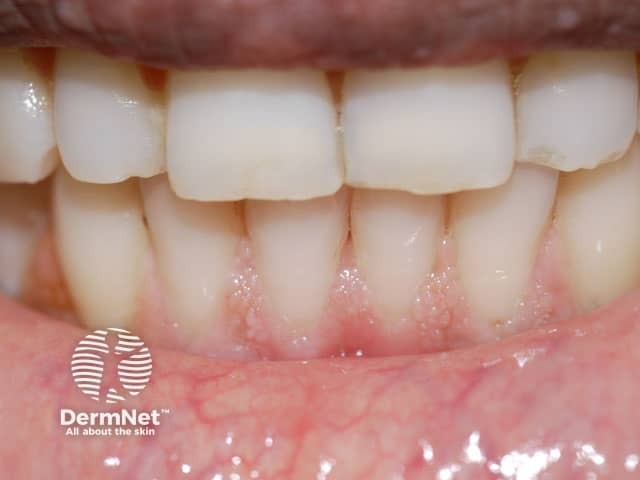

Cobblestone appearence of the gingivae in Cowden syndrome